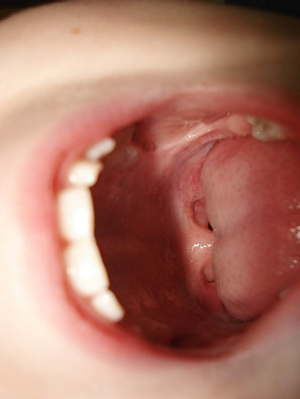

4. 편도결석 치료

편도염은 주로 항생제와 진통제 등의 약물 치료로 관리되며, 반복되거나 심각할 경우 편도 제거 수술을 고려할 수 있습니다. 방법은 결석을 압출하거나 레이저로 편도음와를 줄이는 방법 등이 있습니다.

편도결석은 음식물 찌꺼기와 세균이 뭉쳐 편도 표면에 낀 작은 알갱이입니다. 이로 인해 입냄새가 심해지고, 목에 이물감을 느낄 수 있습니다. 편도결석은 일반적으로 편도염을 제대로 치료하지 않아 발생하며, 입안 청결 유지, 수분 섭취 등이 예방에 중요합니다.